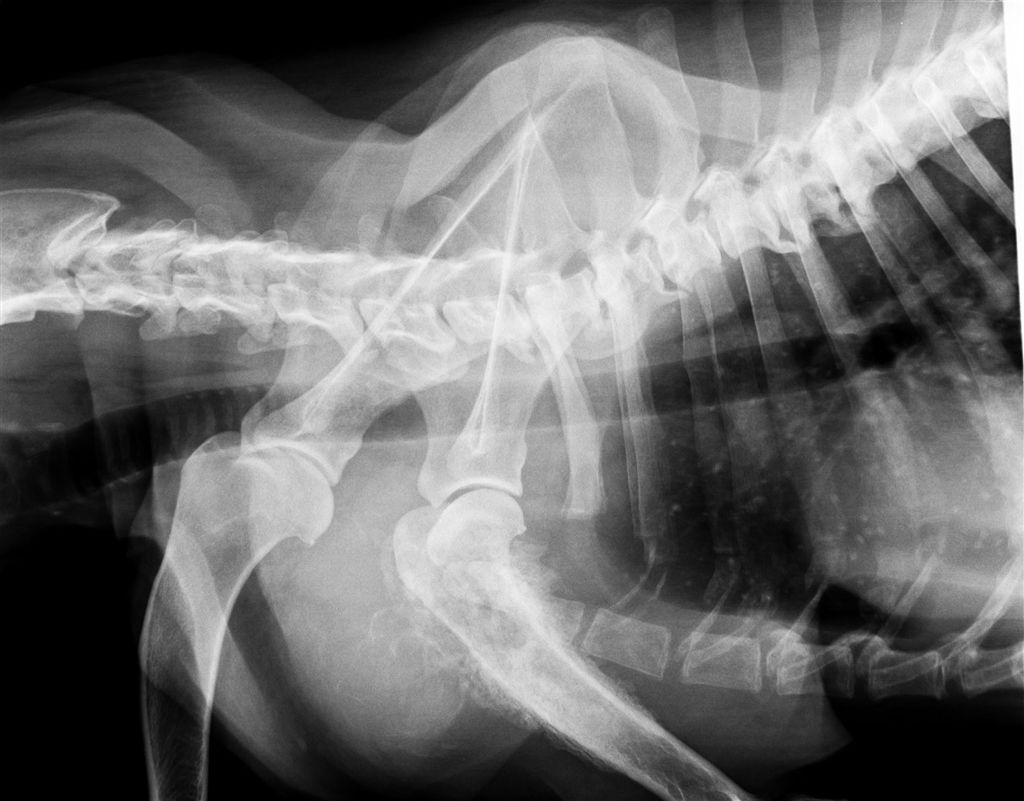

ラブラドール レトリバー 16歳 オス

左前足 肩腫れている

骨肉腫

肺に転移がみられる